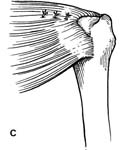

While most people have heard of the rotator cuff, many are unclear about why we have one and how it functions. The term "rotator cuff" refers collectively to a group of four relatively small muscles that surround the "ball and socket" joint of the shoulder. These muscles are called the supraspinatus, infraspinatus, subscapularis and teres minor. (See Fig. 2.) One function of these muscles is to aid in the rotation of the arm around its long axis (as when one throws a Frisbee or passes a plate from side to side). Another, perhaps more important, function of the rotator cuff is to keep the humeral head (the "ball" of the joint, connected to the arm) centered in the shallow glenoid (the "socket" of the joint, which attaches the arm to the body). When the larger muscles around the shoulder (the deltoids, pectoralis, latissimus, and others) move the arm, they tend to impart forces that act to displace the humeral head from the socket. The rotator cuff muscles must contract to keep the ball and socket joint centered. When the cuff muscles become weak, torn, or injured, they can no longer perform this centering function and the abnormal motions affect the normal function of the shoulder. This usually causes pain and weakness with shoulder motion.

- The edge of the cuff tear must be brought back to its normal position without undue tension. This process is accomplished using techniques called mobilization or in larger tears, a technique called margin convergence. (See Fig. 4).

As tears become larger, they deform and the tendon tissue "shrinks". Thus, larger tears need to be refashioned, repaired side-to-side, or "zipped" closed using a technique called margin convergence. This technique is analogous to zippering shut an open tent flap. The rotator cuff tissue is freed from a scarred, retracted position and repaired side-to-side to ‘close the tent flap’ and restore the tissue over the top of the humeral head. (See Fig.4 and Fig.10) The repaired cuff tissue is then fixed to the site it originally tore away from using specially-designed implants called suture anchors. These are metallic or absorbable plastic devices that secure sutures to the bony attachment. The sutures are then sewn through the torn edge of the cuff to complete the repair.